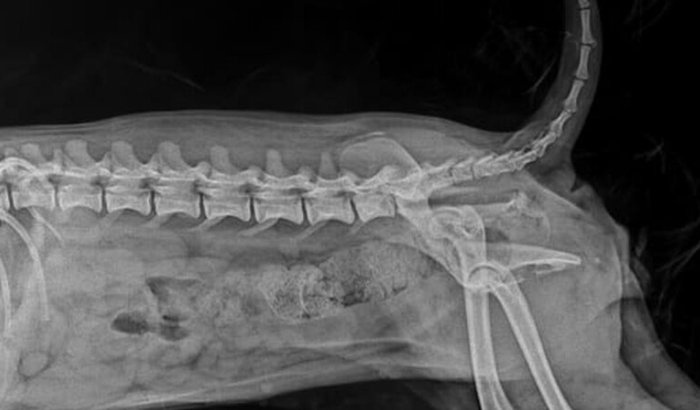

Eu sou a Dejane , minha cachorrinha foi atropela e estou fazendo essa vaquinha para custear os gastos ver tudo

Eu sou a Dejane , minha cachorrinha foi atropela e estou fazendo essa vaquinha para custear os gastos